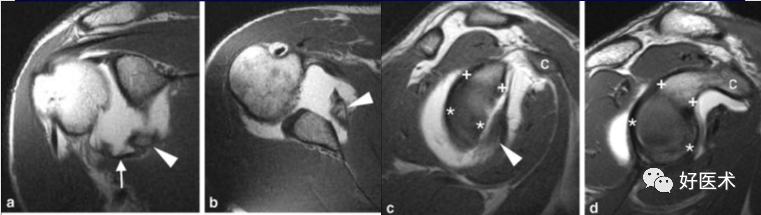

3)完全性撕裂

原发征象:肌腱局部缺如,连续性液体信号横贯肌腱的全层,这使得盂肱关节和肩峰下滑囊相通。

继发征象:

①肩峰下滑膜囊积液,积液在T1WI /PDWI上呈中等信号,T2WI+FS上呈高信号;

②冈上肌肌肉、肌腱结合处回缩(正常位置在肱骨头上方);

③滑囊旁脂肪垫的渗出丢失。

MR 关节造影:局限性或弥漫性充满造影剂的裂隙贯穿肌腱全层,肌腱失去其连续性。

正常、异常肩袖肌腱和邻近软组织结构的MR表现

冈上肌肌腱撕裂可分为全层或部分,部分撕裂又分为下表面(关节面)撕裂、上表面(滑囊侧)撕裂及腱内撕裂。据文献报道,冈上肌肌腱下表面撕裂最常见,可为上表面撕裂的2~3倍,腱内撕裂则最少见。

冈上肌腱不完全撕裂

冈上肌腱不完全撕裂伴肩峰下囊积液

冈上肌肌腱损伤(撞击),肩胛下滑囊积液(肩胛下肌腱损伤?)

冈上、下肌腱撕裂、肩胛下囊积液